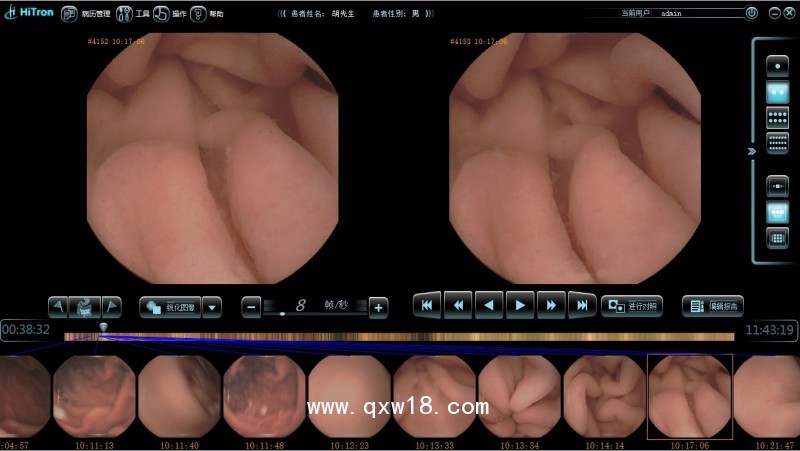

供應(yīng)Hitron膠囊內(nèi)鏡 膠囊內(nèi)窺鏡 膠囊式內(nèi)窺鏡系統(tǒng)產(chǎn)品說明:

? ? Hitron膠囊式內(nèi)窺鏡系統(tǒng)產(chǎn)品由膠囊式內(nèi)窺鏡、數(shù)據(jù)記錄儀、膠囊式內(nèi)窺鏡圖像與報(bào)告處理系統(tǒng)軟件組成。膠囊式內(nèi)窺鏡主要依靠微電子與光學(xué)技術(shù),在人體消化道內(nèi)拍攝圖像,通過無線射頻技術(shù)將圖像發(fā)送到體外,由體外的天線馬甲接收后儲存在數(shù)據(jù)記錄儀中,再上傳至軟件操作平臺進(jìn)行圖像還原和整理,圖像信息供醫(yī)生作為診斷依據(jù)。只需吞服一顆膠囊,就能無任何痛苦的完成消化道的檢查,可對消化道的各種病變起到早期發(fā)現(xiàn),從而進(jìn)行早期診斷和早期治療,及時(shí)避免病變的進(jìn)一步惡化。

即時(shí)顯示:可現(xiàn)場查看膠囊式內(nèi)窺鏡在體內(nèi)的圖像

圖像無損壓縮

在保證圖像質(zhì)量的同時(shí),不造成圖像信息的丟失并減少了需要通過無線傳送的數(shù)據(jù)量,提高圖像拍攝速度,使幀率提高到2幀/秒。

更高分辨率

圖像分辨率可達(dá)480*480,鏡頭分辨率大于8lp/mm,使圖像更精細(xì),更容易分辨出細(xì)節(jié),方便醫(yī)生診斷。

影像增強(qiáng)

采用影像增強(qiáng)技術(shù),使腸道圖像提升對比度后更加清晰。